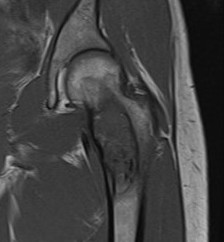

MRI

Low signal intensity T1 / High signal intensity T2